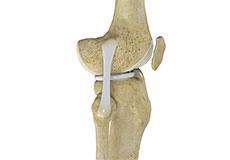

Bones of the Knee

The knee is a hinge joint made up of two bones, the thighbone (femur) and shinbone (tibia). There are two round knobs at the end of the femur called femoral condyles that articulate with the flat surface of the tibia called the tibial plateau. The tibial plateau on the inside of the leg is called the medial tibial plateau and on the outside of the leg, the lateral tibial plateau.

The two femoral condyles form a groove on the front (anterior) side of the knee called the patellofemoral groove. A small bone called the patella sits in this groove and forms the kneecap. It acts as a shield and protects the knee joint from direct trauma.

A fourth bone called the fibula is the other bone of the lower leg. This forms a small joint with the tibia. This joint has very little movement and is not considered a part of the main joint of the knee.

Ligaments of the Knee

Ligaments are tough bands of tissue that connect one bone to another bone. The ligaments of the knee stabilize the knee joint. There are two important groups of ligaments that hold the bones of the knee joint together, collateral and cruciate ligaments.

Collateral ligaments are present on either side of the knee. They prevent the knee from moving too far during side to side motion. The collateral ligament on the inside is called the medial collateral ligament (MCL) and the collateral ligament on the outside is called the lateral collateral ligament (LCL).

Cruciate ligaments, present inside the knee joint, control the back-and-forth motion of the knee. The cruciate ligament in the front of the knee is called anterior cruciate ligament (ACL) and the cruciate ligament in the back of the knee is called posterior cruciate ligament (PCL).